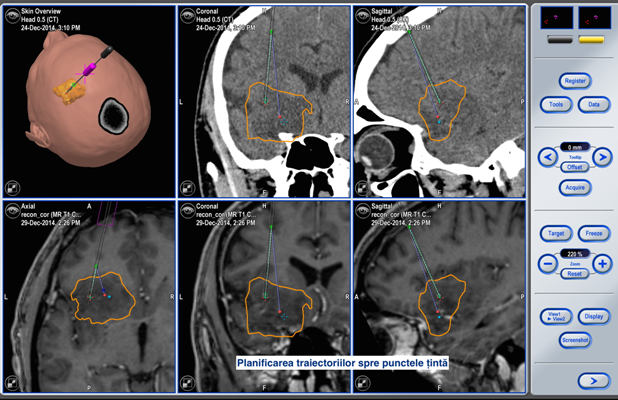

Toate aceste incomodități lipsesc în cadrul biopsiei cu utilizarea neuronavigației fără cadru stereotaxic. Astfel, procedura pentru pacient arată cât se poate de simplu. Pacientul intră în sala de operație fără cadru pe cap și iese de acolo cu procedura de biopsie realizată, localizarea și precizia biopsiei fiind confirmate pe masa de operație.

Pacientul S., a beneficiat de tehnologiile existente în volum deplin. Operația a durat 2 ore. Pacientul și-a revenit după o oră de la intervenția chirurgicală, iar peste o zi a fost externat. Pentru prelevarea biopsiei a fost aleasă o porțiune de tumoare localizată la adâncimea de 13 cm de la suprafață. Locul ales a fost țintit cu precizia de 0,2mm! Acest grad de precizie este suficient pentru toate biopsiile cerebrale, iar în anumite circumstanțe, sistemul poate fi utilizat și pentru tratamentul parkinsonismului.